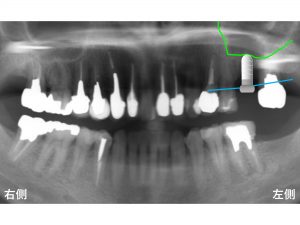

以下が治療後です。

長いインプラントを埋入することができました。

当医院で使用しているインプラントは、世界でもっとも信頼性の高いインプラントの一つであるストローマンインプラント です。